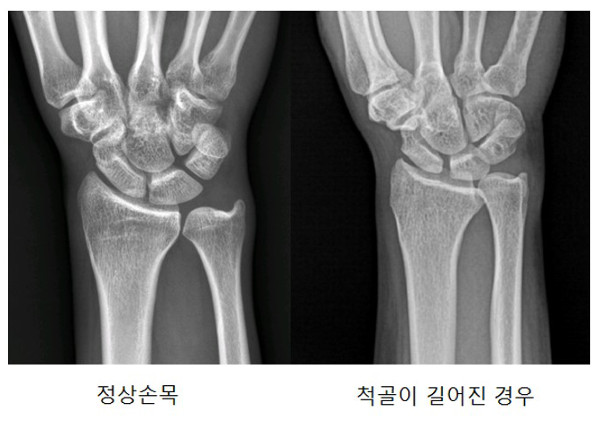

손목 척골단축술: 통증 완화와 기능 회복의 마지막 방법!

손목 척골단축술: 통증 완화와 기능 회복을 위한 혁신적 수술 방법손목 척골단축술의 원리, 적응증, 수술 과정 및 회복에 대해 알아봅겠습니다. 이 혁신적인 수술이 어떻게 손목 통증을 완화하고 기능을 회복시키는지 탐구해보죠. 손목 통증으로 일상생활에 지장을 받고 있다면 손목 척골단축술이 그 해답이 될 수 있습니다. 이 수술은 최근 정형외과 분야에서 주목받고 있는 혁신적인 치료법으로, 많은 환자들에게 새로운 희망을 안겨주고 있습니다. 2022년 대한정형외과학회의 보고에 따르면, 손목 척골단축술을 받은 환자의 85%가 수술 후 6개월 이내에 일상생활로 복귀했다고 합니다. 이 글에서는 손목 척골단축술의 모든 것을 상세히 알아보겠습니다. 손목 척골단축술의 원리와 적응증손목 척골단축술은 척골(ulna)이라 불리는 팔..